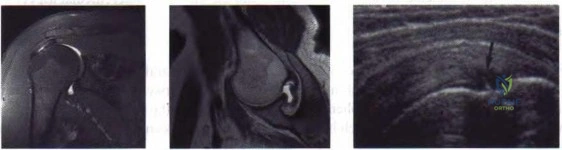

Review the provided imaging.

During a total knee arthroplasty, the surgeon notes that the extension gap is perfectly balanced, but the flexion gap is excessively tight. Which of the following is the most appropriate step to balance the knee?

Review the radiograph.

A patient experiences recurrent posterior dislocations of their total hip arthroplasty. On radiographic evaluation, the acetabular component is found to have 5 degrees of anteversion and 30 degrees of inclination. What is the most appropriate acetabular revision strategy?